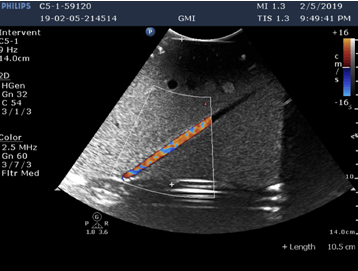

Doppler sensitivity and measurement accuracy measurements, as well as image quality assessment follow the FDA diagnostic ultrasound guidance Clinical safety and effectiveness requirements as well as the JIS T 1501 test standard for imaging performance of diagnostic ultrasound systems.

Reports include Doppler sensitivity of diagnostic ultrasound transducers and systems, including maximum penetration depth, using string and flow phantoms for simulated use, in Color, PW and CW modes. Measurement accuracy includes the accuracy of the distance measurements, lateral and axial resolution, maximum penetration, as well as velocity measurement accuracy in CW and PW modes, among others.